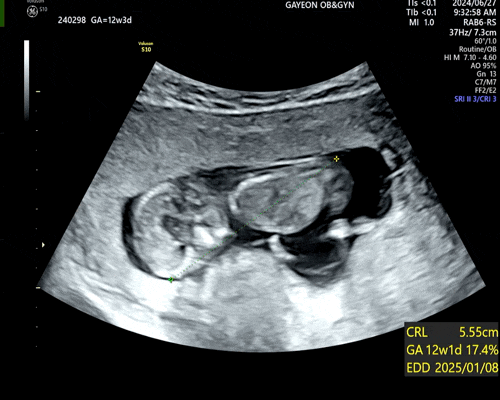

[임신12주] 1차 정밀 초음파&기형아 검사.

24년 6월 27일 떨리는 날이 다가옴. ⭐️1차 정밀 초음파+기형아 검사⭐️ (아침에 정말 별생각 다함) 예약...